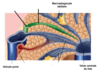

Comment se sépare le pharinx?

- le nasopharynx (voies respiratoires)

- l’oropharynx (en arrière de la cavite buccale)

- le laryngopharynx (réuni à l’oesophage dans sa partie inférieure)